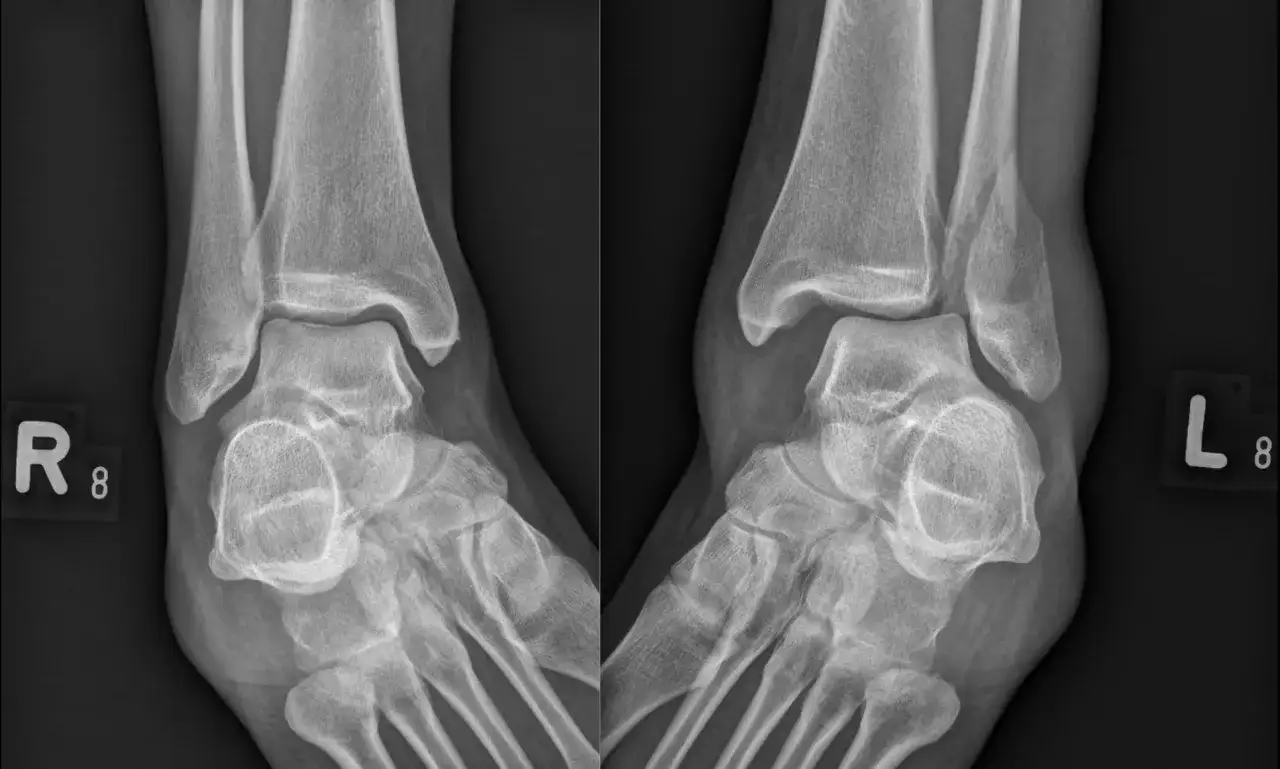

RTG dlaczego prześwietlenie jest absolutnie niezbędne?

Podstawowym i absolutnie niezbędnym badaniem diagnostycznym w przypadku podejrzenia zwichnięcia jest zdjęcie rentgenowskie (RTG). RTG pozwala nie tylko potwierdzić fakt zwichnięcia, czyli trwałe przemieszczenie kości, ale co równie ważne wykluczyć towarzyszące złamania. Przy tak poważnych urazach, jak zwichnięcie, bardzo często dochodzi również do złamań kości, dlatego precyzyjna ocena RTG jest kluczowa dla dalszego planowania leczenia.